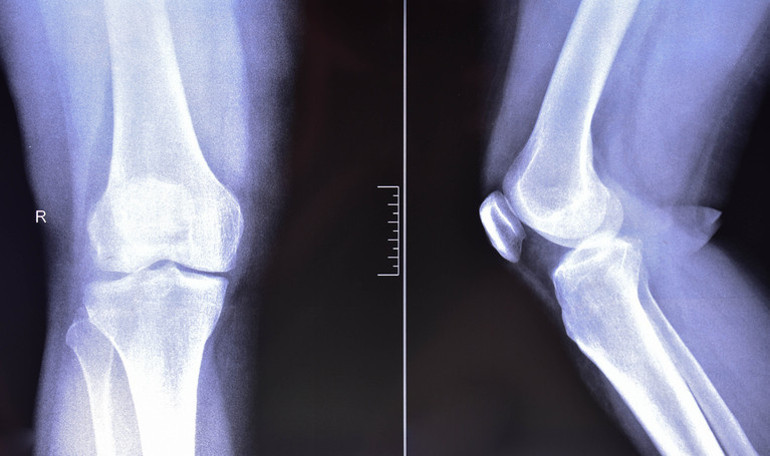

Dev hücreli tümörler kelimenin tam anlamıyla milyonda bir görülen bir hastalıktır. Amerikan Ortopedik Cerrahlar Akademisi'ne göre, sadece 1 milyon kişiden birinde görülür. Bu tümörler kanser olmamalarına rağmen çok agresiftirler ve tedavi edilmezlerse büyümeye devam ederler. En sık bacaklarda, diz eklemi yakınında görülürler ve çevredeki kemikleri de tahrip edebilirler.

Dev hücreli tümörleri diğer kötü huylu kanserlerden ayıran en önemli özelliğin kötü huylu kanserler gibi vücudun başka yerlerine yayılmamaları ve sadece bulunduğu kemikte çürüme yapması olduğunu belirten Dr. Tarık Elma, dev hücreli tümör olan hastaların, genellikle tümörün bulunduğu kemikte ağrı ve şişlik şikâyeti ile doktora başvurduklarını, bu sebeple kırık veya incinmeyle sıklıkla karışabileceğini ifade etti.

Elma, burada erken tanının çok önemli olduğunu, çünkü bazen hastalanan kemiklerdeki bu ağrılarını önemsemezse bu tümörün kemiği içten içe yiyerek zayıflatacağını ve kemiğin içini boşaltacağını, içi boşalan kemiğin de çok ufak bir darbede veya ani bir hareket sonucunda ciddi şekilde kırılabileceğinin altını çizdi. Erken tanı konması durumunda ise tedavisinin oldukça basit olduğunu ve yapılacak cerrahi müdahaleler ile tümörün temizlenerek kemiğin tekrar güçlendirilebileceğini sözlerine ekledi.